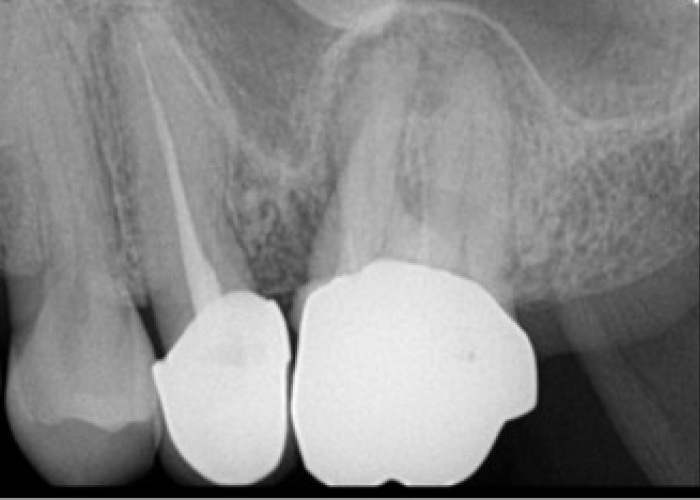

신경치료 전후 사례

• 치료 전

치료 후

• 치료전

치료후